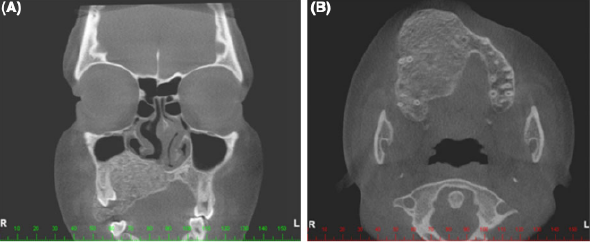

13

Q

What are characteristics of fibrous dysplasia?

A

• Bone replaced by fibrous tissue

• Affects craniofacial bones

• Painless enlargement- stops after adolescent

• Genetic anomalies

• Can associated with cutaneous/endocrine syndomes

How well did you know this?

What is this?

Fibrous dysplasia